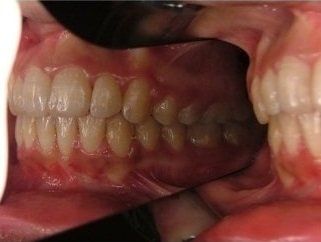

L’ortodonzia non dimentica neanche l’importanza dell’estetica e la sicurezza che un bel sorriso può portare. Per questo un apparecchio può avere come obiettivo anche quello di riportare il profilo facciale nella posizione più corretta possibile e di restituire al paziente un aspetto migliore, oltre che la fiducia in se stesso.

- può migliorare l'aspetto e la funzione dei denti;

- la capacità di parlare e masticare può essere migliorata;

- denti più dritti facilitano lo spazzolamento e per questo sono meno soggetti a carie e altre patologie.